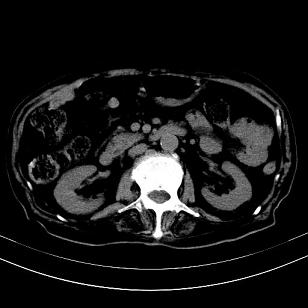

标题: CT19407:肝内还是肝外原发性肿瘤??

男,63岁,高血压病史40余年,

来源-右侧肾上腺。

考虑右侧肾上腺巨大占位;恶性?

肝内多发低密度找;转移瘤?

另:右肾结识,多发小囊肿。

考虑右肝后叶肝癌(部分外生)伴肝内多发性转移;右侧肾上腺区恶性肿瘤并肝转移待排。

考虑右侧肾上腺肿瘤并肝内多发转移。右侧肾上腺呈“八”字形,包括内侧枝及外侧枝,内侧枝受压,考虑外侧枝原发肿瘤。”